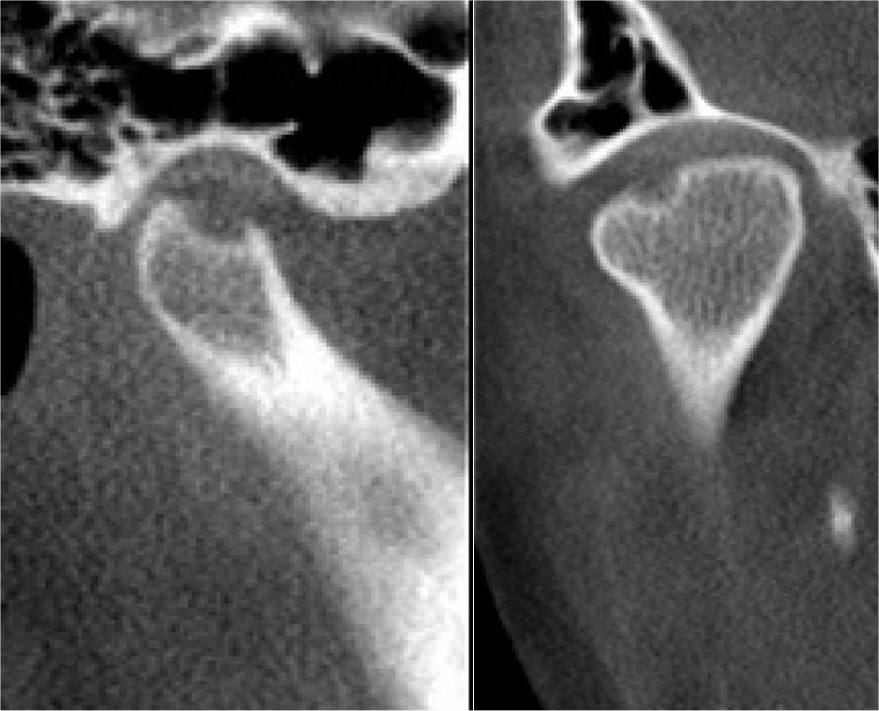

CBCT TMJ Imaging

Evaluation of the TMJ’s, teeth, sinus, jaws, and airway to identify the contributing factor of TMJ disorders.